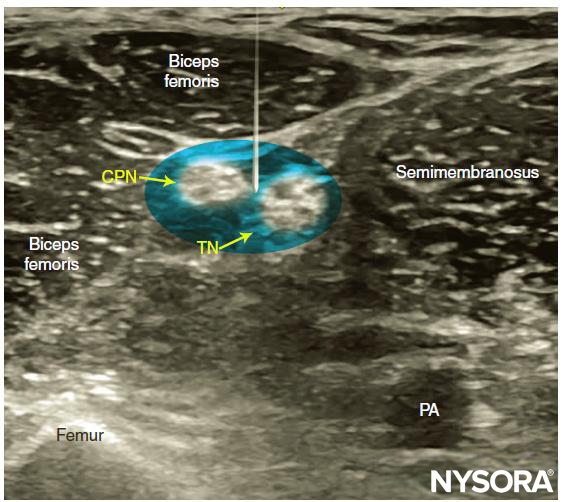

The goal is to inject the local anesthetic within the common connective tissue (Vloka’s) sheath that envelops the TN and CPN. Alternatively, separate nerve blocks of TN and CPN can be performed.

Reverse Ultrasound Anatomy for a popliteal sciatic nerve block with needle insertion in-plane and out-of-plane and local anesthetic spread (blue). TN, tibial nerve; CPN, common peroneal nerve; PV, popliteal vein; PA, popliteal artery; SmM, semimembranosus muscle; BFM, biceps femoris muscle.

It is recommended to perform the nerve block at the level where TN and CPN start diverging but are still in the common sciatic nerve (Vloka’s) sheath. For the lateral approach, a skin wheal is made on the lateral aspect of the thigh 2–3 cm above the lateral edge of the transducer, and the needle is inserted in plane in a horizontal orientation from the lateral aspect of the thigh and advanced toward the sciatic nerve (Figures 7 and 8).

For the posterior approach, the needle is inserted in plane from lateral to medial (Figure 9) or out of plane (Figure 10). If nerve stimulation is used (0.5 mA, 0.1 msec), the contact of the needle tip with either branch of the nerve usually is associated with a motor response of the calf or foot. Once the needle tip is placed within the common sciatic nerve sheath, 1–2 mL of local anesthetic is injected to confirm the proper injection site. Such injection should result in a distribution of local anesthetic within the sheath, and separation of the TN and CPN within Vloka’s sheath (Figure 11).

When local anesthetic injection does not appear to result in a spread inside the sciatic nerve sheath and around the sciatic nerve components, additional needle repositions and injections may be necessary. Correct injection is recognized when local anesthetic spreads proximally and distally to the site of the injection around both divisions of the nerve, which can be documented by observing the spread of the local anesthetic within Vloka’s sheath proximal to the site of injection. A single injection of local anesthetic typically suffices.